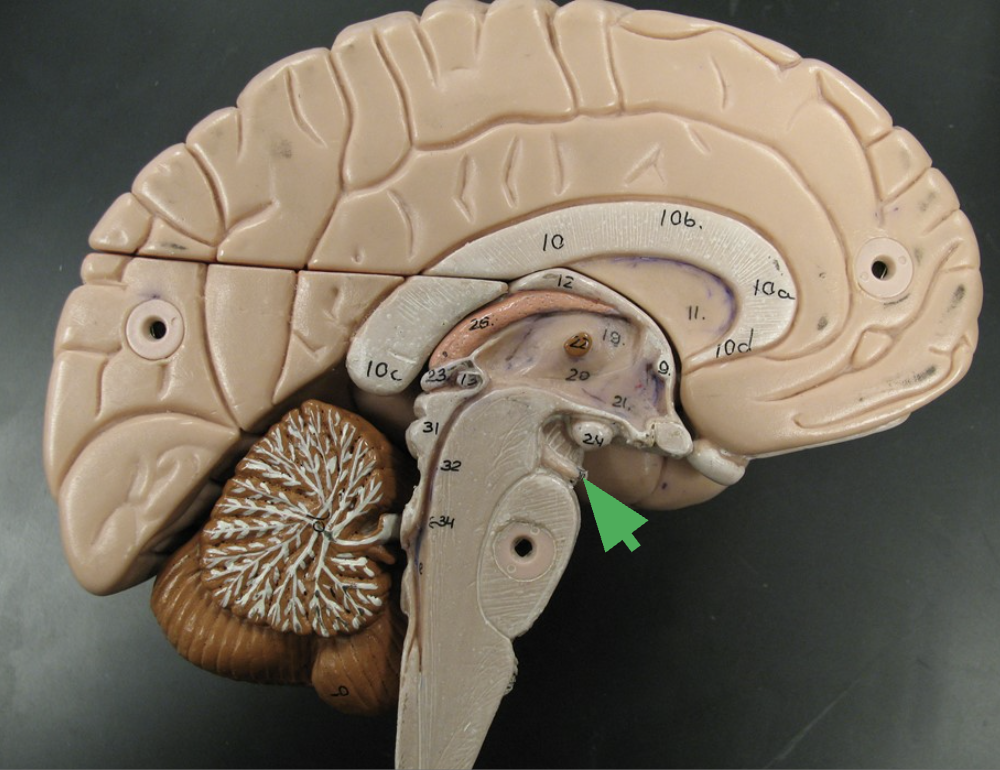

Medulla oblongata

What does the medulla oblongata do?

Nuclei are involved in heart rate, blood pressure, breathing, sneezing, and vomiting.

What does the medulla oblongata contain?

Contains motor tracks ventrally and sensory tracks dorsally.